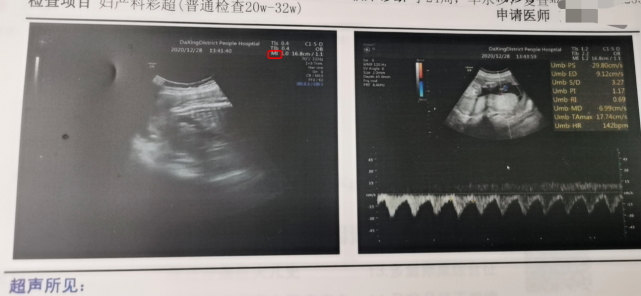

胎心率

看胎心率,140左右的一般是男宝宝,150以上的一般是女宝宝。这个在生大宝的时候,是这样的,每次胎心都是150以上,没有以下的时候,也不知道是否就赶巧了。这胎就是150以下,再用二宝来检测下,看看准不准。